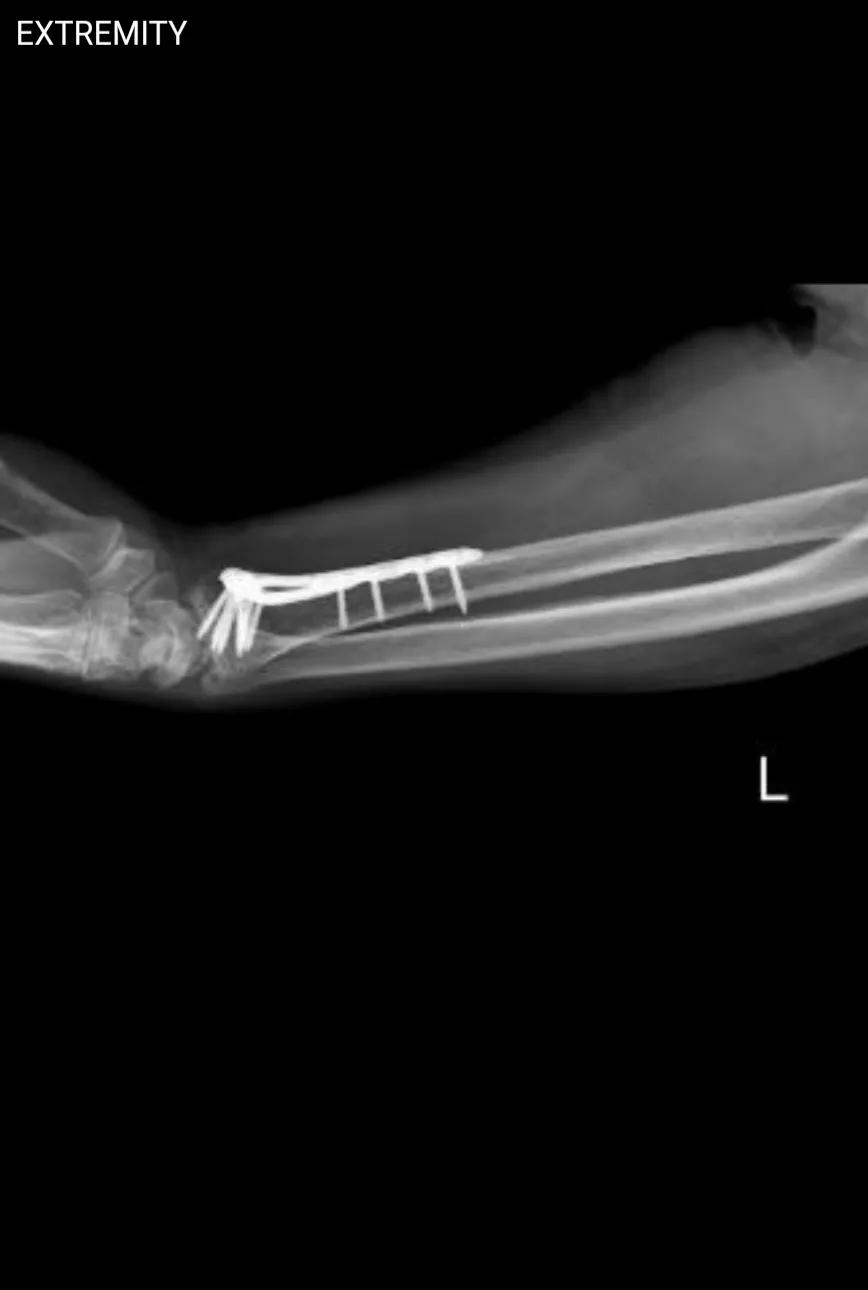

螺钉是11颗? 今天接诊了一位桡骨远端骨折术后的患者来我院取内固定。拍了X线后,我反复数螺钉,怎么数都是11颗。可有人说有12颗,有人说13颗,甚至还有人说10颗。原本以为这手术是我院做的,还打算调手术记录看看,结果发现并非如此。我也顾不了那么多了,我认定就是11颗,不服来辩。